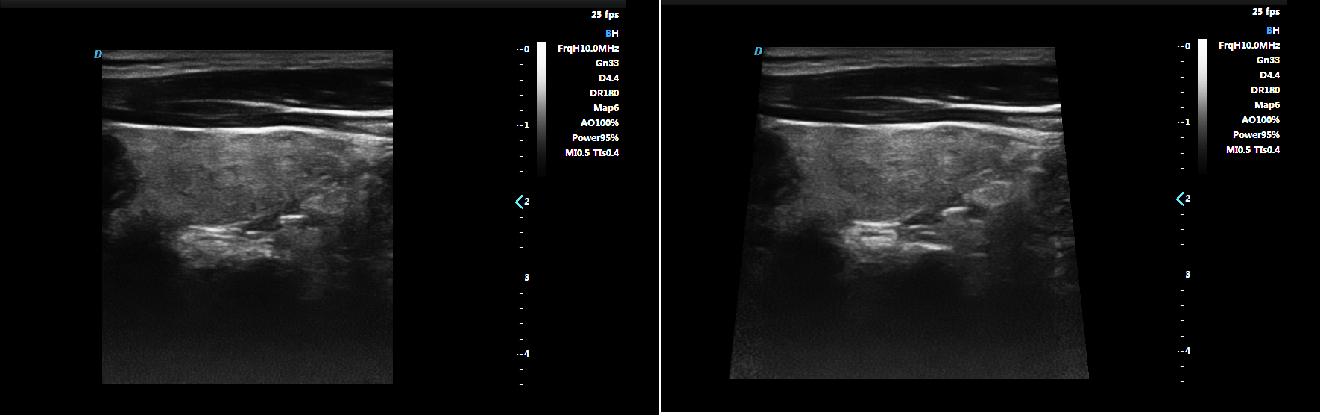

Micron Imaging Technology

Micron imaging technology, real-time tracking of specific signals at the edges of different tissues, to achieve edge enhancement,

and monitor each pixel at the same time; optimize the internal signal of the organization and perfectly integrate the edge

information and the internal pixel information of the organization to restore the real and delicate, excellent level contrast

Two-dimensional image.